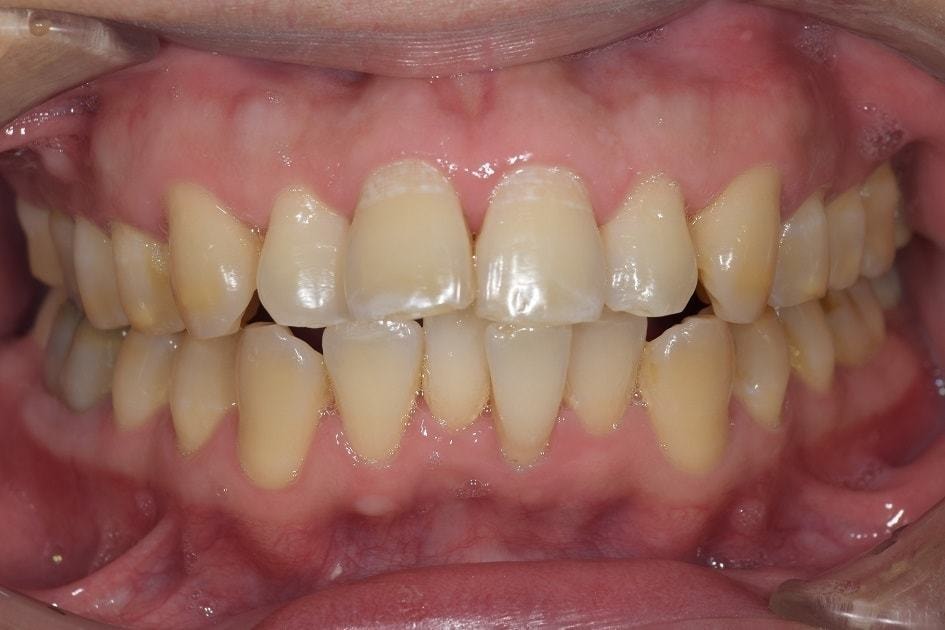

こちらの写真は、当院での基本的な歯周病治療を行った後の状態になります。

赤かった歯茎がある程度健康なピンク色に変化していることがよくわかるかと思います。ここから本格的な歯周病治療が必要ですが、本格的な治療を始める前にある程度炎症のとれた歯茎にしておくことは、非常に大切です。

家を建てる時に、基礎工事をしっかり行うと思いますが、歯も一緒で、歯茎が基礎だと思っていただくと、分かりやすいかと思います。粘土の上に家を建てても長持ちしないのと一緒で、歯も基礎である歯茎や根の治療をしっかりしていないと、その後の治療も長持ちしません。その為、当院では緊急性のある痛みを除く治療以外は、歯周病の治療をまずは優先させて行っております。